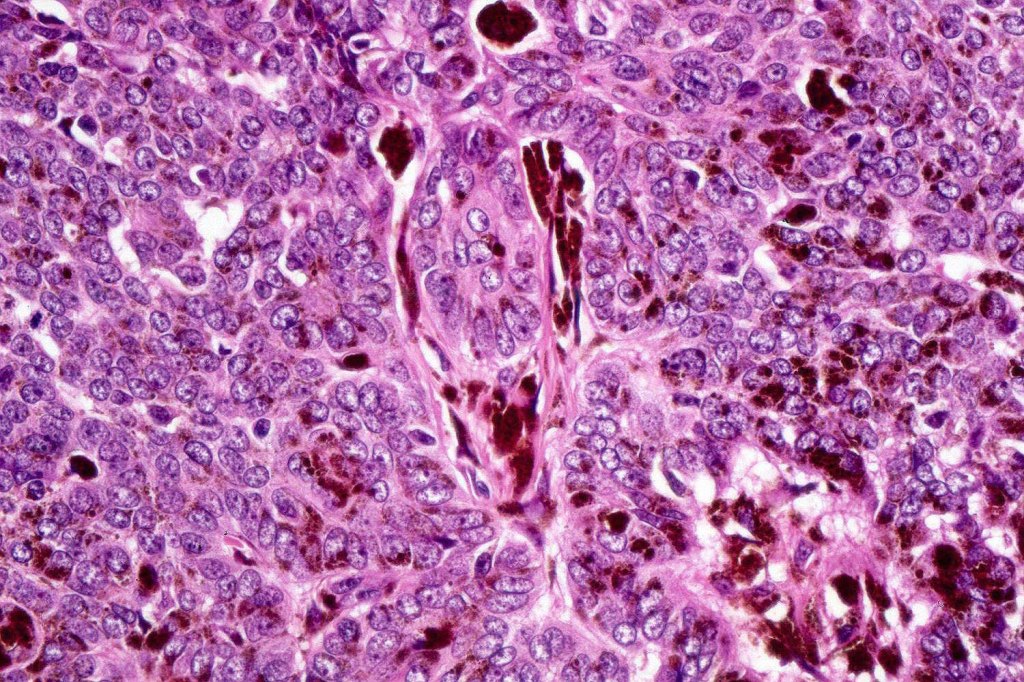

•Uniform basaloid cells with peripheral palisading and often marked mitotic activity

•No pleomorphism

•Merkel cells are commonly present

•CK20, PHLDA1 +ve Merkel cells+